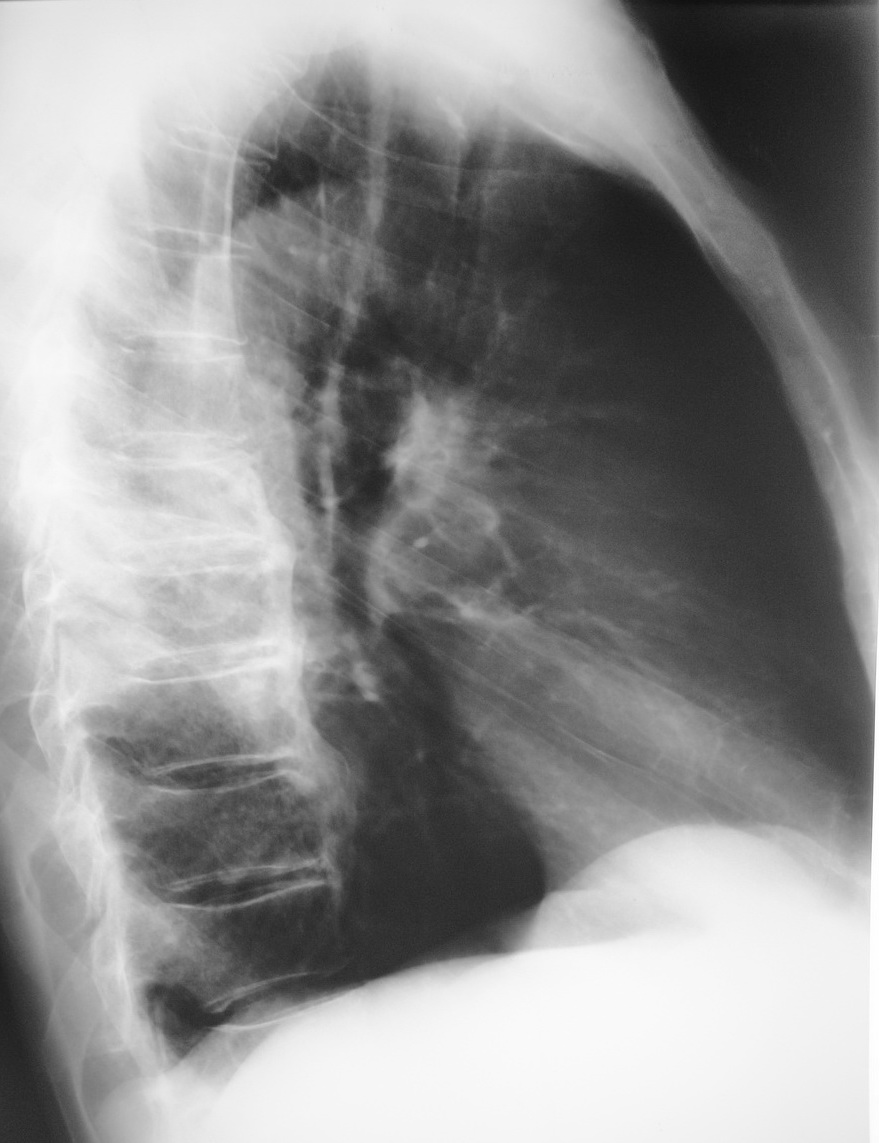

боковая

... боковая - явно не инвалида случая!..

Снимки выполнены на разных аппаратах разными людьми с интервалом 3-4 дня..

Зато, на "этой боковой" хорошо виден перелом грудины....

к своему, многому стыду вот боковая...